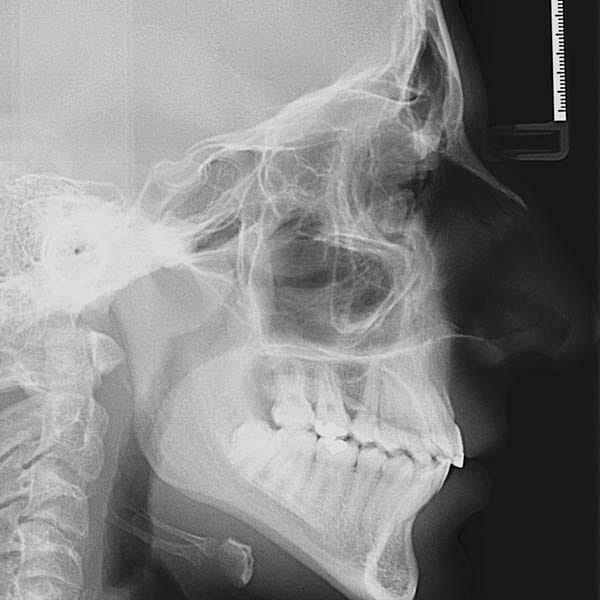

This young man visited me due to the severe protrusion in his teeth. Upon examination, I noticed the presence of molars with large fillings, which are not expected to endure for a long time.

So we decided to extract these two molars and use their space to return the front teeth back, in the end, our friend regained his beautiful smile again.